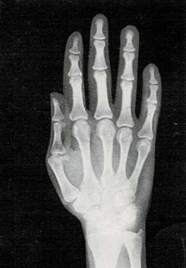

Mi madre me respondió: “Una razón de que lo encuentres blando es que sus huesos no son tan duros como los tuyos. Los niños, al nacer, tienen muy pocos huesos duros. Los huesos de su esqueleto se componen sobre todo de cartílago. Pero las células óseas trabajan sin descanso, y por ello sus huesos crecen y se endurecen muy deprisa. Tus huesos son más largos y duros que los del niño. Los huesos seguirán creciendo y se endurecerán hasta tus veinte años.

El médico me respondió: “Tu muñeca tiene ocho huesos. Pero no todos crecen a la vez. Los huesos de la muñeca de algunos niños crecen más deprisa o más despacio que los de otros niños. Pero los huesos de la muñeca crecen a un mismo ritmo en todos los niños sanos. Si los huesos de tu muñeca salen bien en la radiografía, quiere decir que el resto de los huesos de tu cuerpo también están bien.”

En ella ya se ven claramente los ocho huesos.